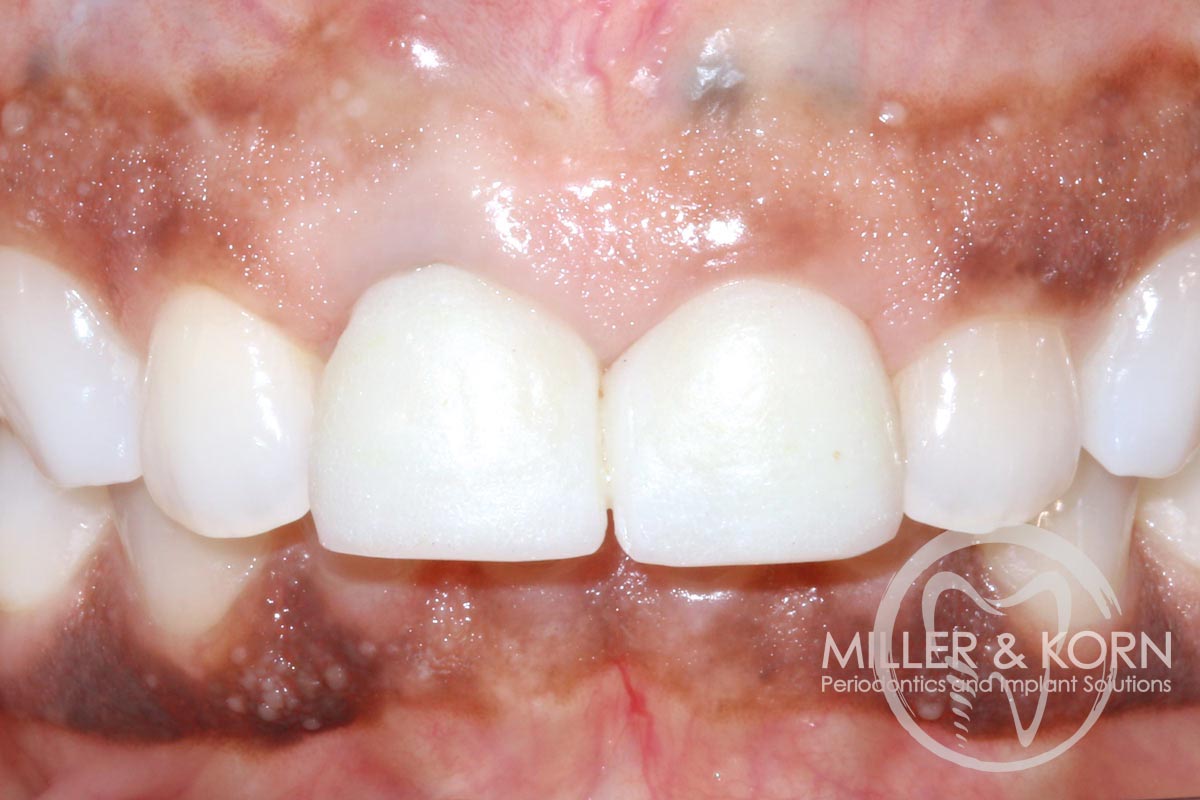

1/22 - 60-year-old female patient presented with a chronic infection on tooth #11. Since she has a high lip line matching the gingival margins of the adjacent central incisor and creating a root eminence is extremely important. For these reasons, the treatment of choice was an allograft bone ring enabling immediate placement of the dental implant with simultaneous regeneration of her ridge.Immediate implant placement and regeneration of ridge using an allograft bone ring and Jason® membrane - Drs. Miller and Korn

2/22 - She experienced trauma as a child and had fractured both tooth #8 and 9 which had been crown several times for esthetics.Immediate implant placement and regeneration of ridge using an allograft bone ring and Jason® membrane - Drs. Miller and Korn

20/22 - Smile one-week post insertion of final prosthesisImmediate implant placement and regeneration of ridge using an allograft bone ring and Jason® membrane - Drs. Miller and Korn